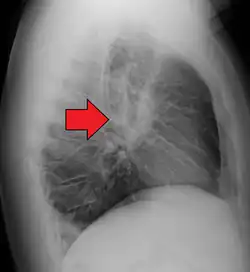

-

Hilar adenopathy especially on the person's left (AP CXR) -

Hilar adenopathy especially on the person's left (lateral CXR) -